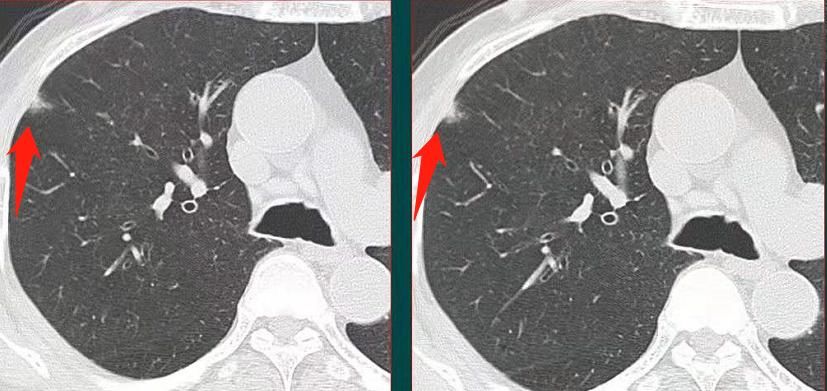

像这位60多岁的男性,没有症状,体检发现右肺斑片状影,边界不清,看起来很像一点炎症。

但他抗炎治疗后3-4个月复查显示,病灶没有消失,并且有缓慢增大的趋势:

狡猾的狐狸也藏不住自己的坏尾巴,果断手术切除,病理是浸润性粘液腺癌。